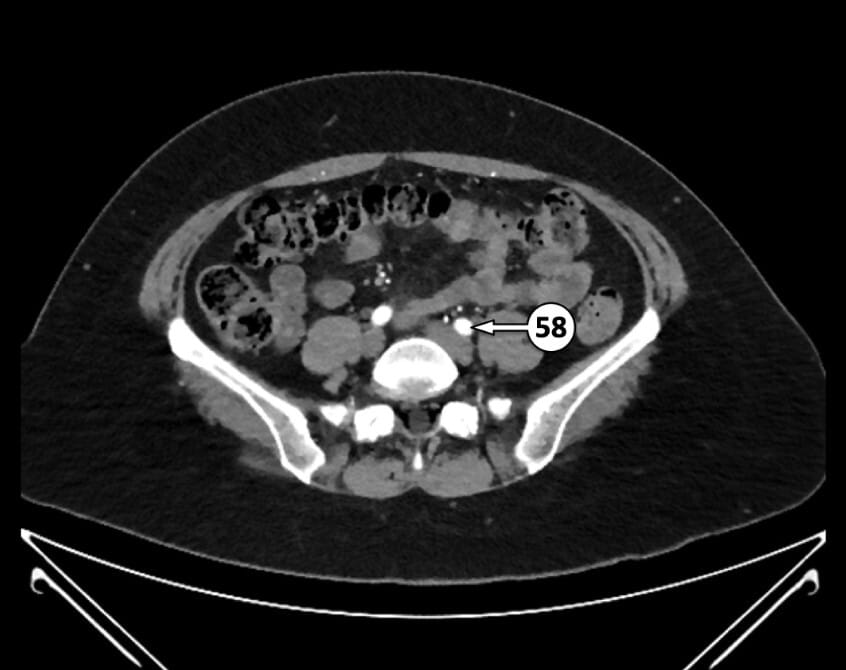

58. left common iliac artery